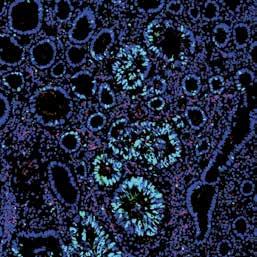

Cover photo: Dr Dilys Leung is a Postdoctoral Research Fellow in the Cabrini Monash University Department of Medical Oncology. Her research on breast cancer organoids is a major focus of the department’s translational research program, performed at the Monash Biodiscovery Institute (BDI) in collaboration with Professor Helen Abud and Dr Thierry Jardé.

In the past year, a generous legacy by the late Peter Richard Hicks is funding Dr Dilys Leung’s research into breast cancer organoids, an advanced laboratory breast cancer culture model that will drive drug discovery research and identify new treatments for breast cancer.

Organoids are “mini-3D tumours” that are created in the laboratory, and perfectly mimic the patients tumour they were developed from. Organoid technology is cutting-edge and can provide a unique approach to personalised cancer treatment, allowing

us to understand every individual metastatic breast cancer in detail, and test and find the appropriate treatment for every patient.

The Cabrini-Monash Breast Cancer Organoid Program is only one of two in the world that have successfully grown organoids from breast cancer cells, but organoids have only been developed from primary breast tumours. This innovative study will be the first of its kind in the world exploring the development of metastatic breast cancer organoids. Once mastered, the process could be made available to all women with metastatic breast cancer, and the eventual aim would be to commercialise the process.

Above: Dr Dilys Leung and Dr Thierry Jardé at the at the Monash Biodiscovery Institute (BDI).